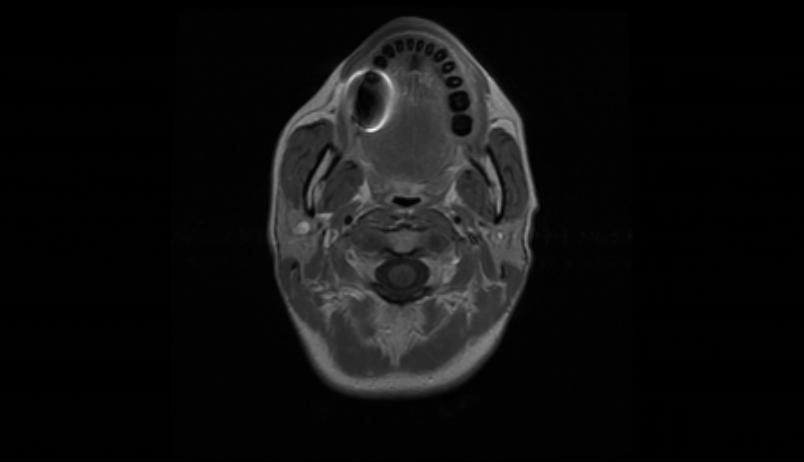

MRI of the cervical and thoracic spine showed a diffuse, intramedullary abnormal signal extending from the medulla down to approximately the mid-thoracic level. There was swelling in portions of the spinal cord, particularly in the lower cervical cord where there was contrast enhancement (Figure 1 [Fig. 1], Figure 2 [Fig. 2], Attachment 1 [Att. 1]). The MRI of the brain was normal.

Figure 1: MRI of the cervical spine, sagittal view: contrast enhancement in the lower cervical cord